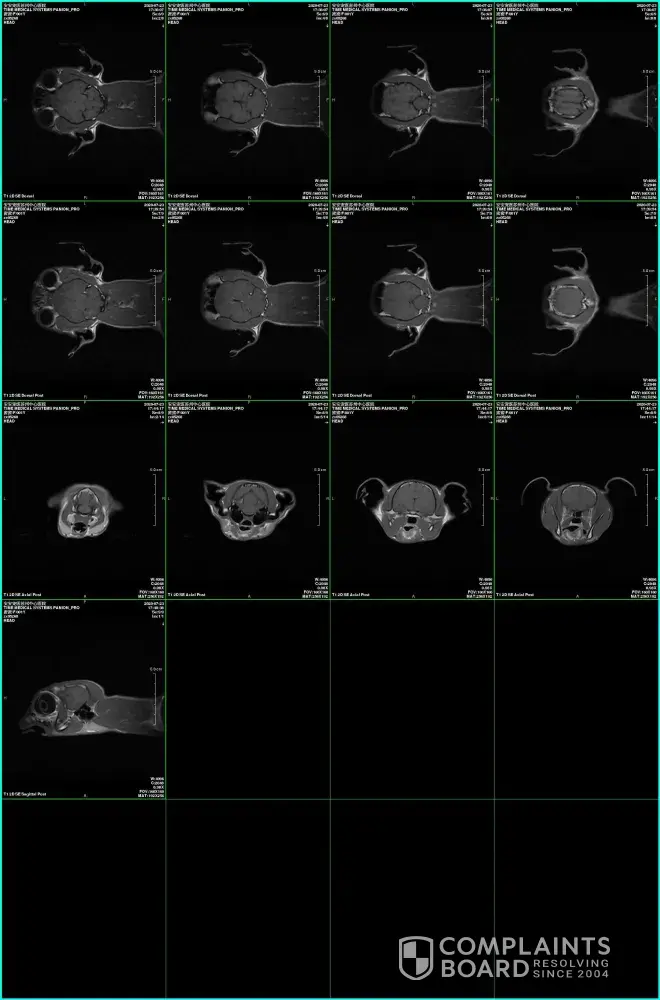

Starlite Rags Ragdoll cat with primary epilepsy

Hi everyone, please think carefully before you adopt a lovely ragdoll from this cattery. She might have PRIMARY EPILEPSY!!! Me and my boyfriend adopted Misty, a lovely chocolate bicolor ragdoll girl, from Starliterags last November and everything was fine until Misty turned to 1 year old. On July 22, Misty had her first sudden seizure and it caused her to...